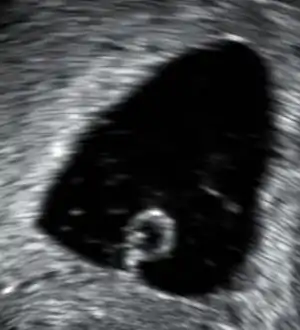

An anembryonic pregnancy (also called an "empty sac" or "blighted ovum") is a condition where the gestational sac develops normally, while the embryonic part of the pregnancy is either absent or stops growing very early. This accounts for approximately half of miscarriages. All other miscarriages are classified as embryonic miscarriages, meaning that there is an embryo present in the gestational sac. Half of embryonic miscarriages have aneuploidy (an abnormal number of chromosomes).[48]